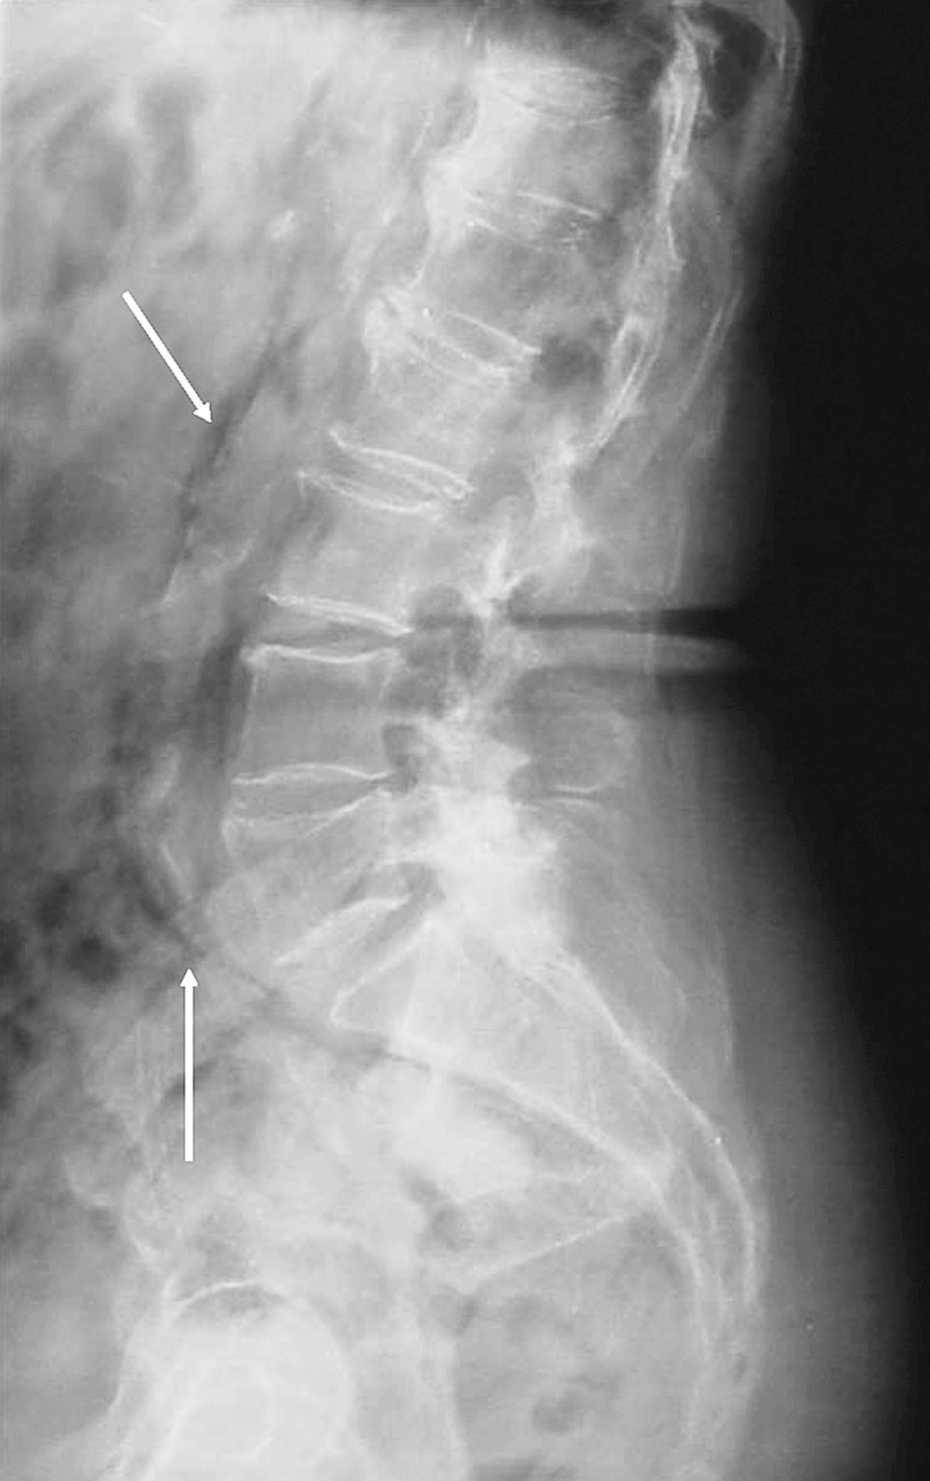

Mujer de 74 años que consulta por lumbalgia izquierda irradiada a miembro inferior izquierdo y dolor tenue en fosa ilíaca izquierda sin signos de irritación peritoneal ni fiebre, tras 15 días de tratamiento con antiinflamatorios no esteroideos, prescritos en dos servicios sanitarios extrahospitalarios. En el servicio de urgencias de nuestro centro se le practicó analítica de orina y radiografía de tórax (normales), analítica sanguínea (13.700 leucocitos y fórmula normal). En la radiografía de raquis lumbar, además de importante espondiloartrosis, se objetivó aerograma en localización atípica (fig. 1). Con el diagnóstico radiológico de neumorretroperitoneo, se le realizó de urgencia una tomografía computarizada abdominopelviana con contraste, que lo confirmó (fig. 2; flechas finas); además, se visualizaba mínimo neumoperitoneo (fig. 2; flechas gruesas) y enfermedad diverticular de sigma, cuya perforación se evidenció durante el ingreso. La evolución fue favorable con tratamiento conservador y desapareció la imagen en la revisión en consultas externas.

Fig. 1. Flechas: aire periaórtico.